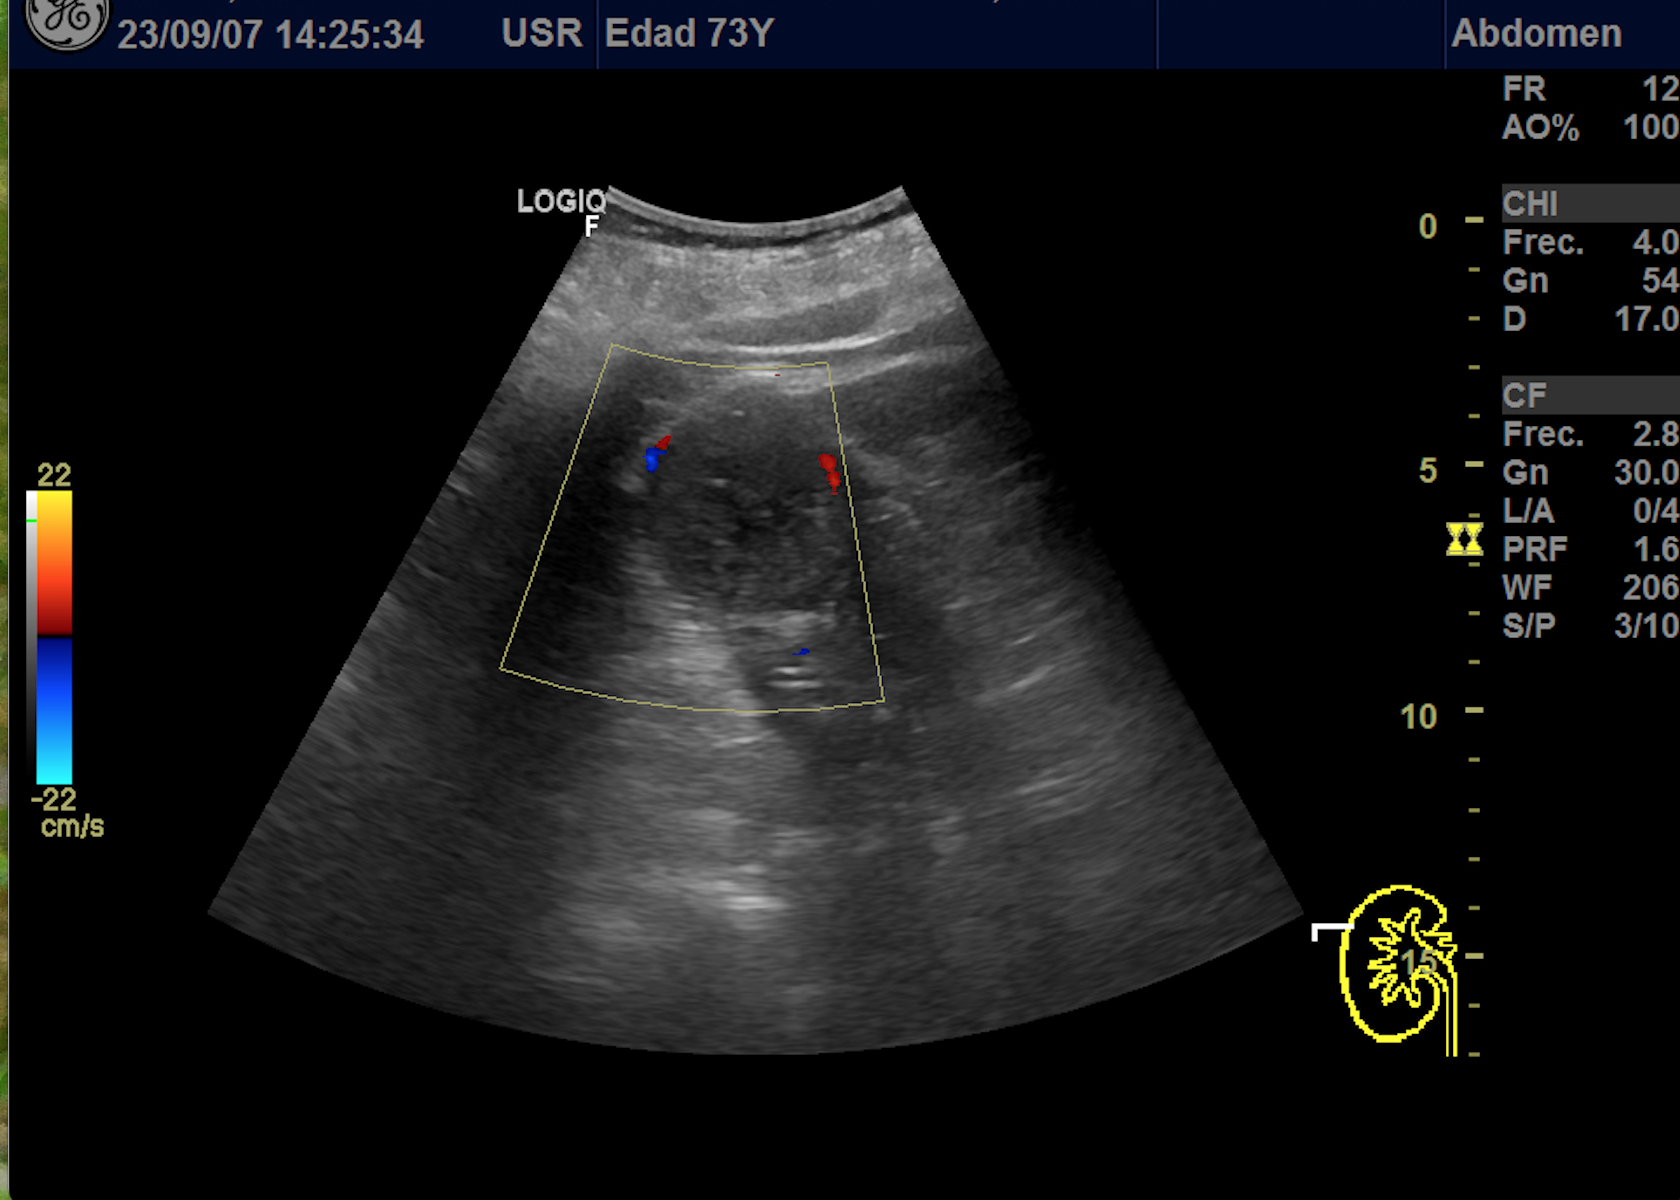

Hallazgos ecográficos

En polo superior de riñón derecho se observa una imagen redondeada, bien delimitada, isoecoica con un área central hipoecoica con vascularización periférica y central de 4,1 x 4,18 x 4,94 cm.